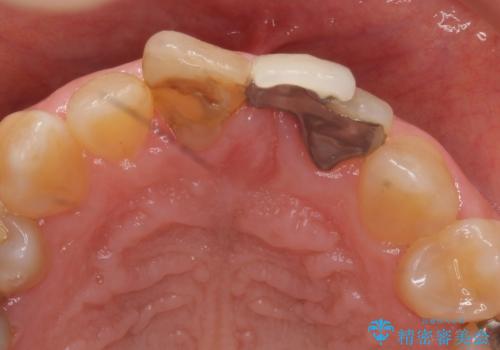

- 前歯の歯並びや色が気になるといらっしゃった方の症例です。

前歯4本をオールセラミッククラウンで補綴することで、歯の並びや色の改善を行いました。

今回用いたオールセラミッククラウンはジルコニアフレームという白い素材の上にセラミックを盛っているため、審美性が非常に高いのが特徴です。

また、ジルコニアは人工ダイヤモンドの材料にも使われているほど高い強度を持っており、そのためオールセラミッククラウンは審美性だけでなく、奥歯やブリッジの補綴も可能とするクラウンです。